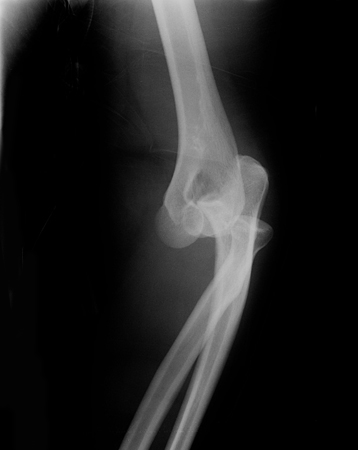

Lateral x-ray view of a posterolateral elbow dislocation

Personal collection of Dr Paul Novakovich